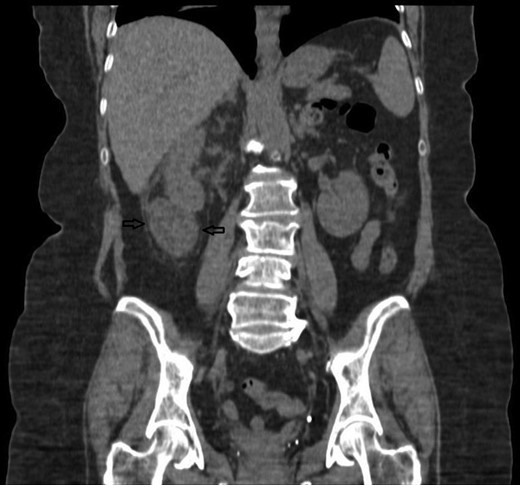

Despite intravenous antibiotics, after 72 h, the patient reported ongoing right loin pain and with persistently raised WCC at 16.6. A decision was made to proceed with a computerized tomography (CT) scan. This showed a bi-limbed right lower pole staghorn calculus measuring 29 × 16 mm associated with a 53 × 56 × 33 mm fluid collection within the right perinephric space. This was associated with inflammatory stranding abutting the lower pole in keeping with a urinoma secondary to a ruptured lower pole calyx, which was not dilated at the time of the scan (Figs 3 and 4).

A CT sagittal view, showing the calculus in the lower pole calyx and the collection below the kidney.